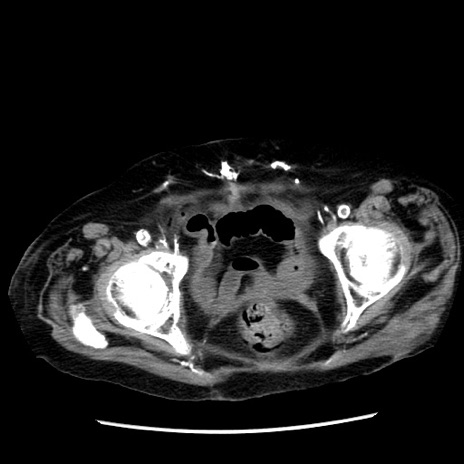

症例14(横断像)

【症例】 90歳代女性

【主訴】 腹痛・嘔吐

【現病歴】今朝から左側腹部痛を認めた。 経過観察していたが、嘔吐を認めたため来院。

【既往歴】 子宮癌術後

【身体所見】 意識清明、BP 127/54mmHg、P 98bpm Sp02 95%(RA)、BT 35.8°C、腹部平坦・軟腸ぜん動音聴取良好、右下腹部圧痛(+) 反跳痛なし

【データ】WBC 9800、CRP 0.46